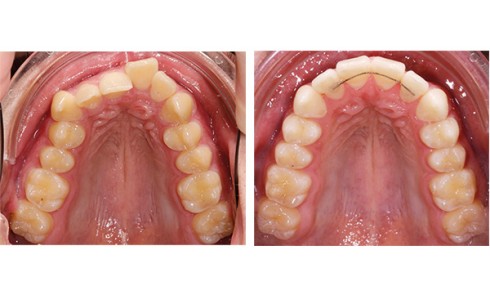

La patiente est une adulte de 22 ans présentant une rétrognathie mandibulaire associée à une endoalvéolie mandibulaire avec un défaut...